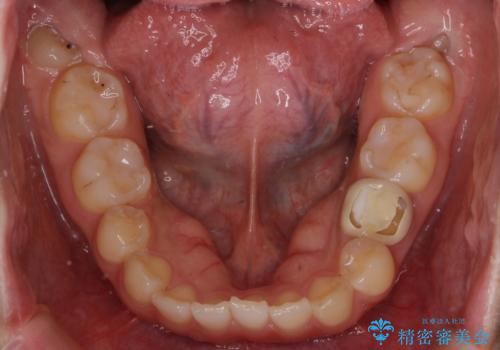

左下に乳歯が残っていましたが、被せ物に穴が空いている状態でした。

乳歯は抜かずに保存的な治療を行いました。

乳歯はまだぐらついたりしていない状態だったため、しっかり虫歯を取り、根の治療も行いました。